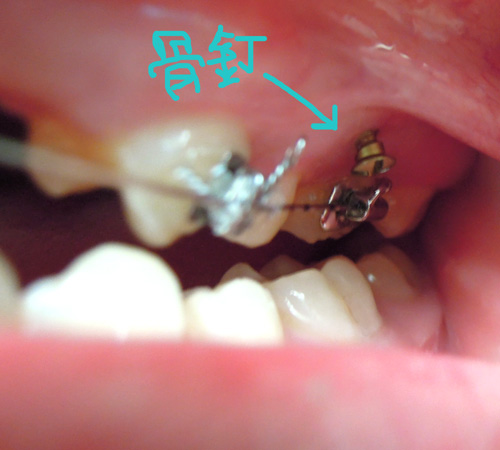

恩 …..,的確如院長所說的,還真的不會痛耶! 我以為會有那種鑽進去的感覺,看來剛剛打入的麻醉藥已發揮?!以下就讓大家看看骨釘長怎樣囉!

我想這次上顎的左右兩側的骨釘(英文:TAD ( Temporary Anchorage Device),是為了下次做準備吧!? 話說我已經戴矯正器戴了半年之久,上顎看起來還是很凸,院長是該讓我看到明顯的進度了吧!?